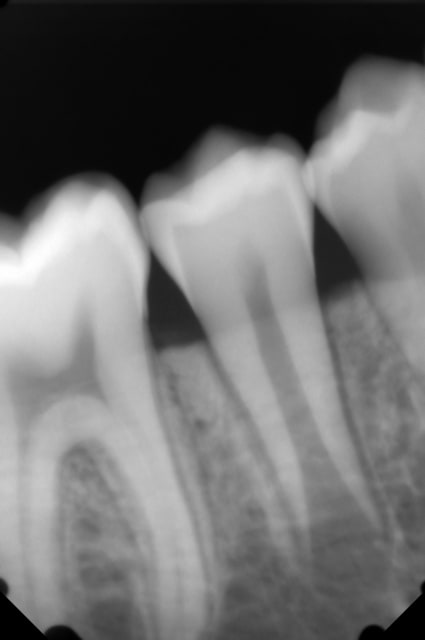

Aujourd'hui j'ai reçu un garçon de 13ans, toutes les dent temporaires sont tombées sauf la 75, j'ai fait une radio et la 35 est présente, sauf que la 75 n'a pas commencé sa rhizalyse semble-t-il.

Je pensait extraire la 75 pour "stimuler" l'éruption de la 35, qu'en pensez-vous?

Je joint la rétro de la 75/35 et de la 45 pour que vous visualisiez l'édification radiculaire.

- Au vu de l’édification radiculaire de la 45 (2/3) et en considérant que celle de la 35 est symétrique, il est temps d'avulser la 75.